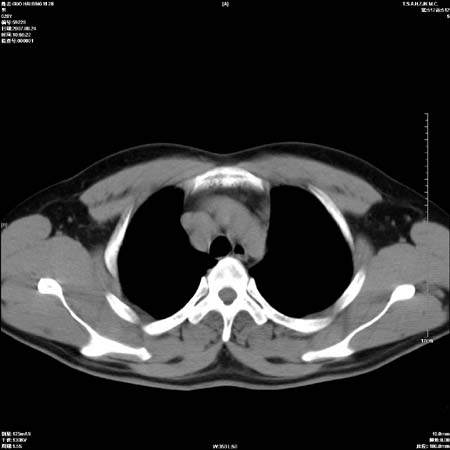

左肺门区软组织肿块,左肺上叶支气管开口消失,纵隔内见肿大淋巴结,考虑左中心型肺部,可以做纤支镜取病理确认.

支持左上叶中央型肺癌伴纵隔淋巴结转移.

左上叶中央型肺癌伴纵隔淋巴结转移

肿块形态影像支持左上叶中央型肺癌伴纵隔淋巴结转移。

左肺门区分叶状软组织肿块,纵隔内有肿大淋巴结,诊断肺癌应该问题不大。